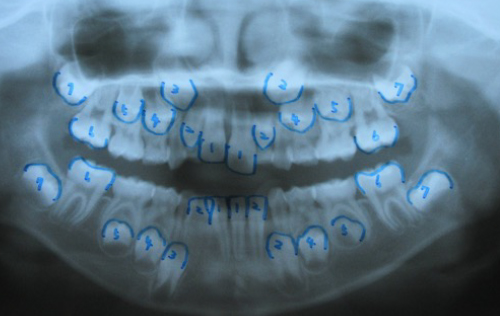

②パノラマレントゲン像

西村歯科医院 医院ブログ

智歯以外は、永久歯は全て存在しています。智歯に関しては、将来 出来てくる場合が有り、智歯の生え方や智歯の深さによりますが、矯正で動かない場合,又は、後戻りの原因になる場合は、

西村歯科医院 医院ブログ大学での抜歯紹介も必要な場合があります。その時は、矯正による抜歯になりますので、自費治療になり、目安として、1本約15,000円必要になります。また、上顎の歯が、密集しており、上顎骨の劣成長(狭い成長)が考えられます。この事は、上顎骨劣成長→鼻腔狭窄→鼻閉→口呼吸習慣に至る傾向にあります。「いびき」・睡眠時無呼吸症候群・寝起きが悪い・中耳炎・夜尿症・などの原因になり易くなります。)